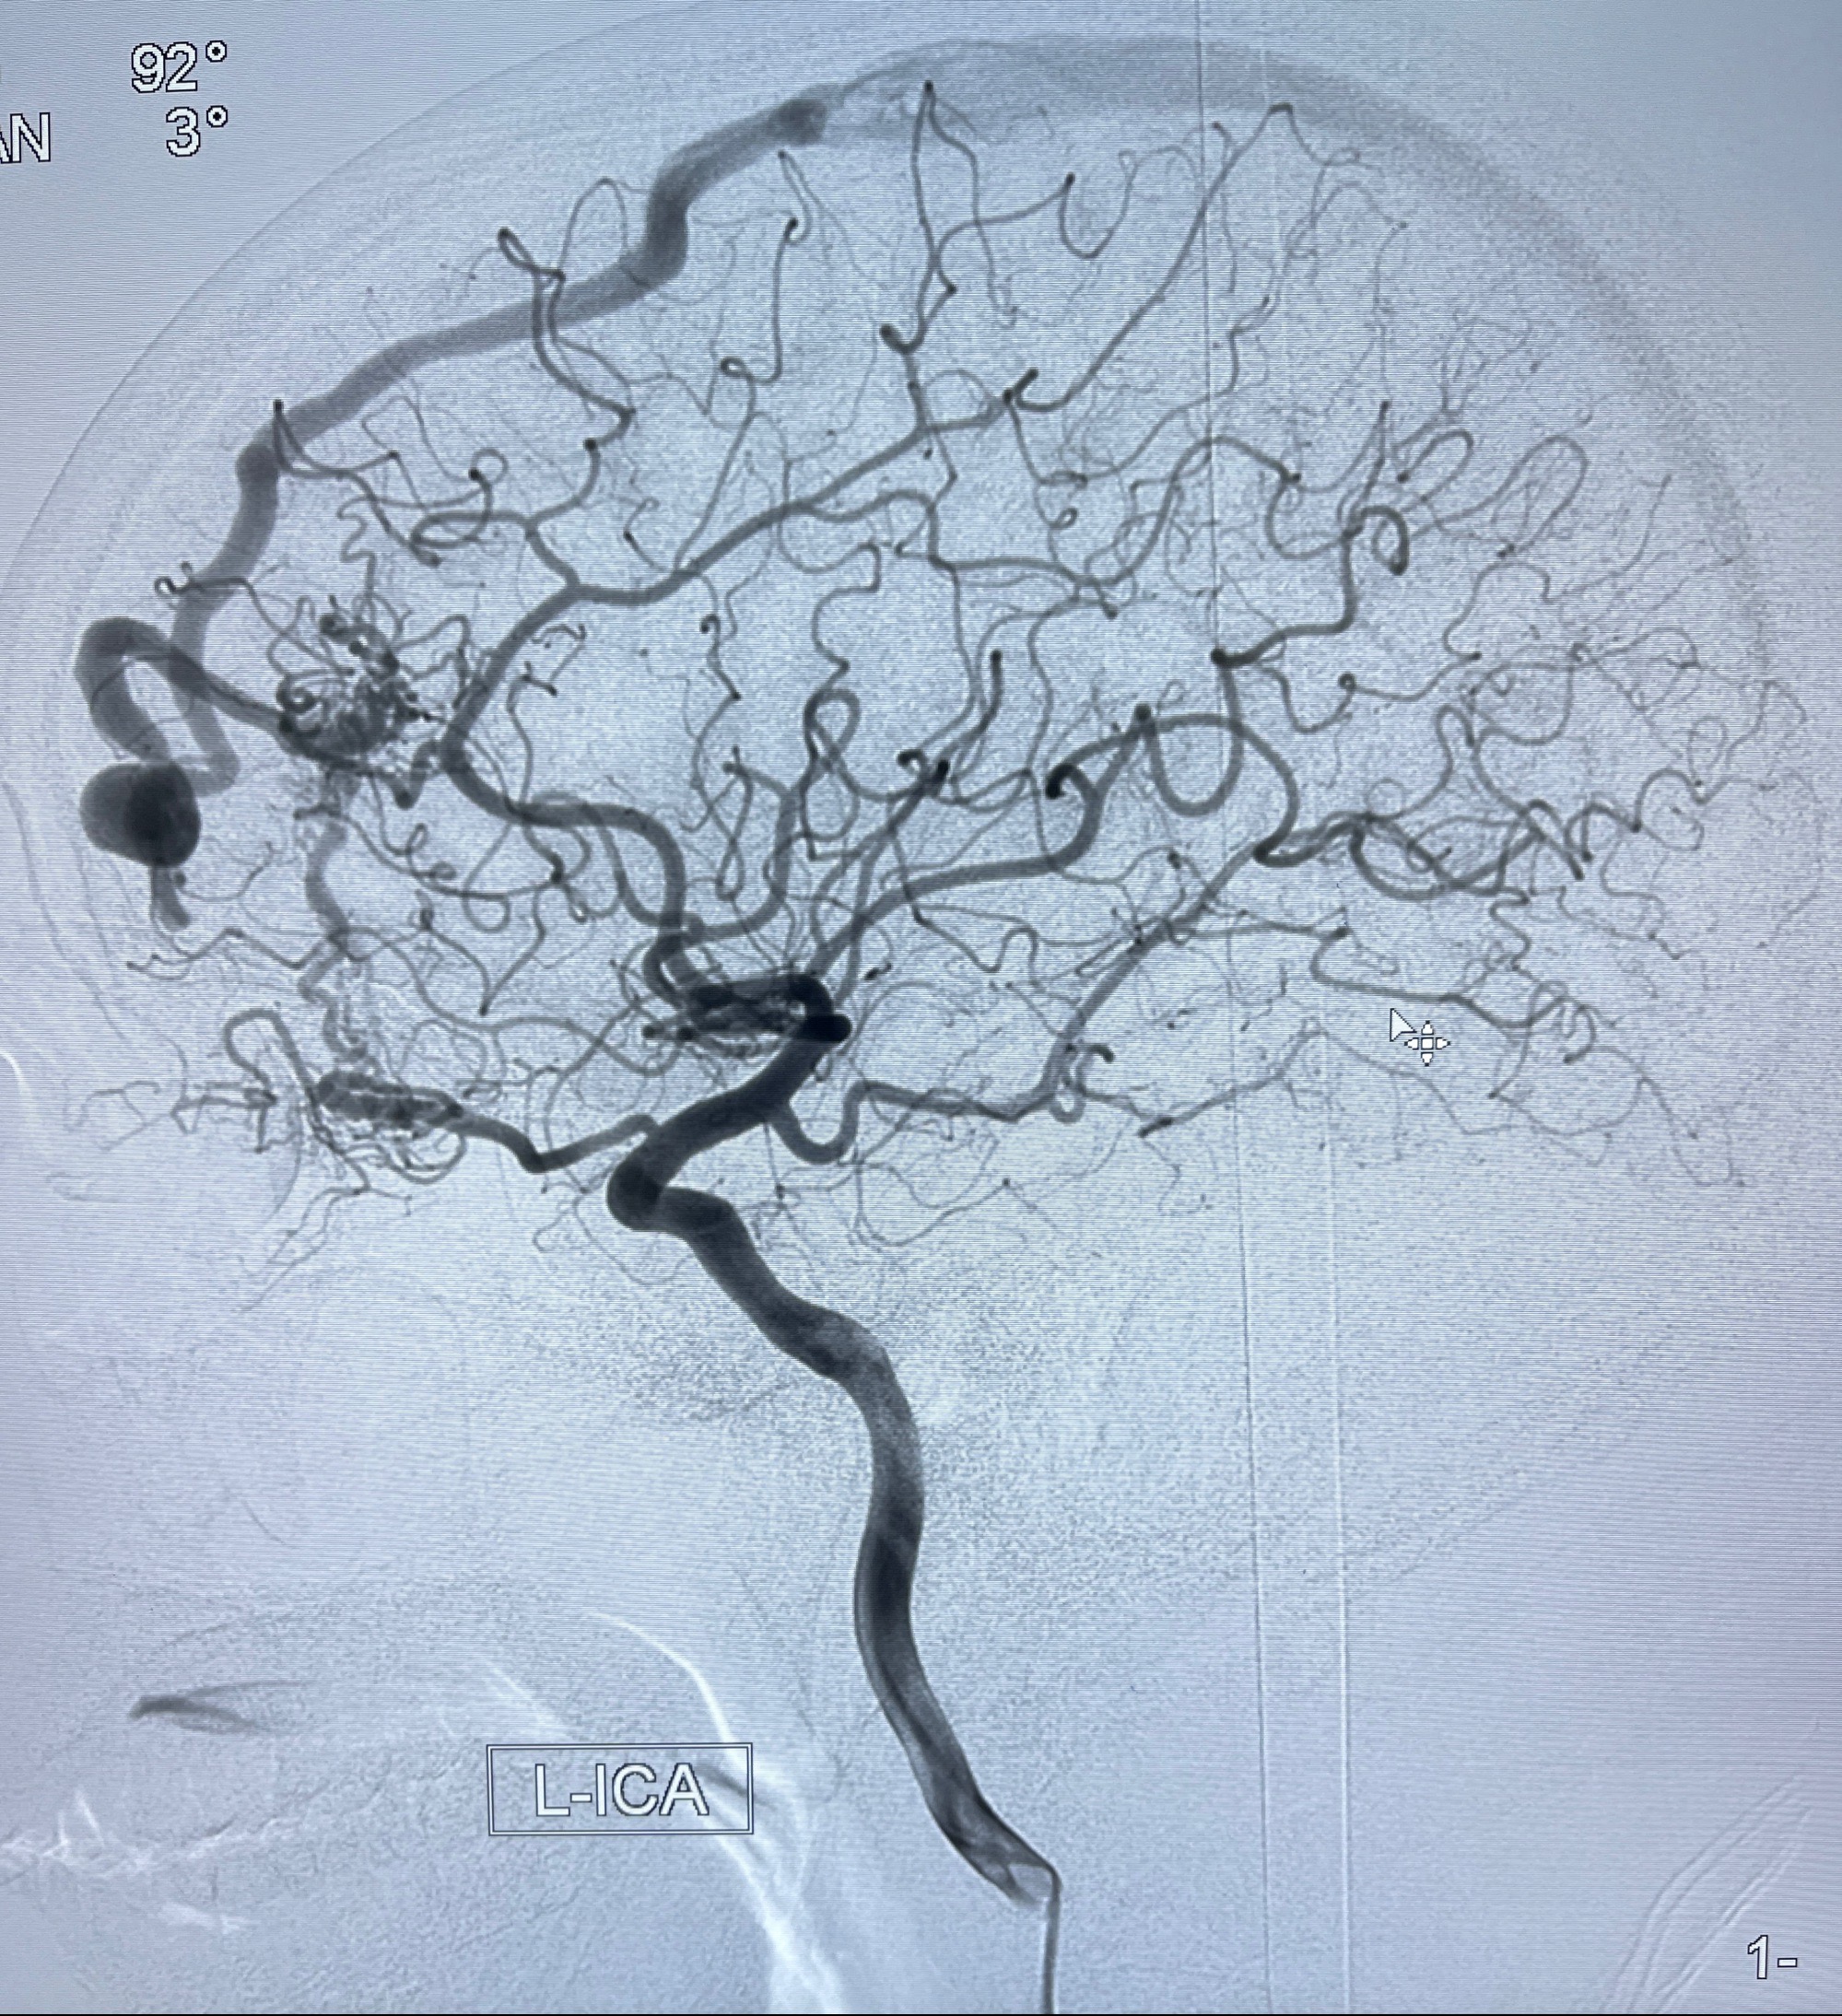

2023年8月21日]景德镇市第一人民医院脑血管造影检查,提示:主动脉弓、双侧颈总动脉、锁骨下动脉造影未见异常,左侧大脑前动脉静脉瘘。

2023-09-13全脑血管造影:前颅底硬脑膜动静脉瘘,供血动脉为双侧胼周动脉、眼动脉脑膜支,静脉向上矢状窦方向引流